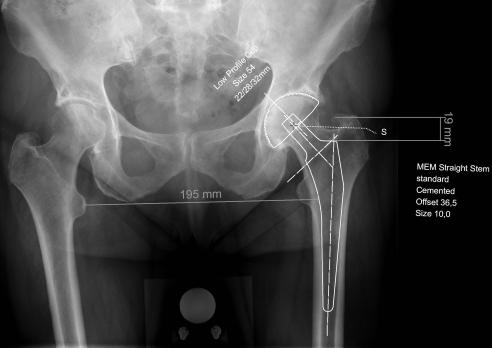

De totale heupprothese Lees meer over De totale heupprothese De totale heupprothese

De totale heupprothese is een van de meest succesvolle operaties omdat het de vaak forse functionele beperkingen en pijnklachten ten gevolge van coxartrose kan doen verdwijnen. De fysiotherapeut heeft een belangrijke ondersteunende rol in het conservatieve en preoperatieve behandelingstraject, de indicatiestelling en het postoperatieve herstel. Daarnaast is het belangrijk om eventuele complicaties vroegtijdig te herkennen. Dit artikel beoogt inzicht te geven in de oorzaken van coxartrose, de indicatiestelling voor een totale heupprothese, de verschillende typen heupprothesen, de verschillende benaderingen en stappen tijdens de operatie, de nabehandeling en de mogelijke complicaties.